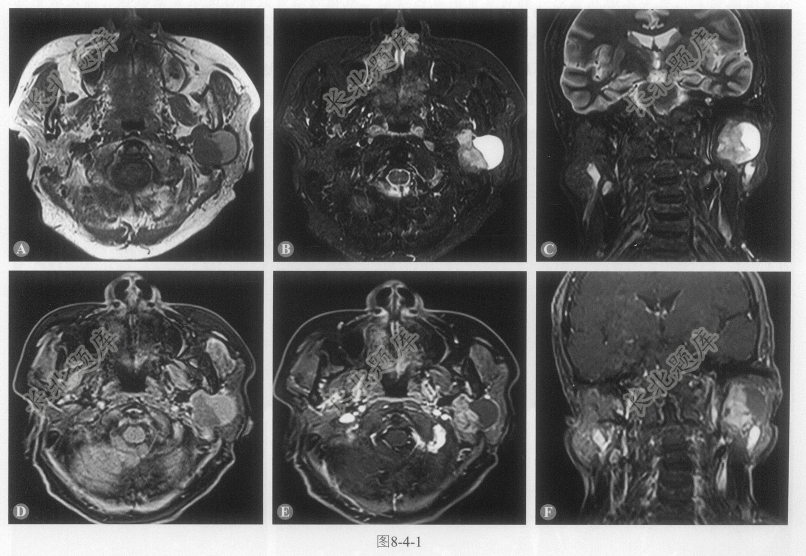

- [材料题] 患者女性,67岁,发现左耳下包块1年,查体:左侧耳垂下部扪及包块,质韧,活动欠佳,边界欠清。MRI图像如图8-4-1。

- 多项选择题1.患者的影像学表现包括:

A、病灶位于左侧腮腺深叶

B、病灶呈囊实性,实性部分T

WI等信号、T2WI脂肪抑制序列呈稍高信号,囊性部分T

WI呈稍高信号、T2WI呈不均匀高信号C、增强后病灶实性部分呈不均匀明显强化

D、病灶边缘有包膜

E、病灶与翼内肌之间脂肪间隙存在

- 多项选择题4.该病典型的MRI特征性表现:

A、T2WI不均匀高信号,增强扫描明显强化

B、因病变的异质性,各种成分的生长速率不同,故常表现为分叶状

C、病灶周围可见包膜,部分包膜不完整

D、肿瘤内水分子扩散受限不明显,ADC值高于恶性肿瘤,但低于腺淋巴瘤